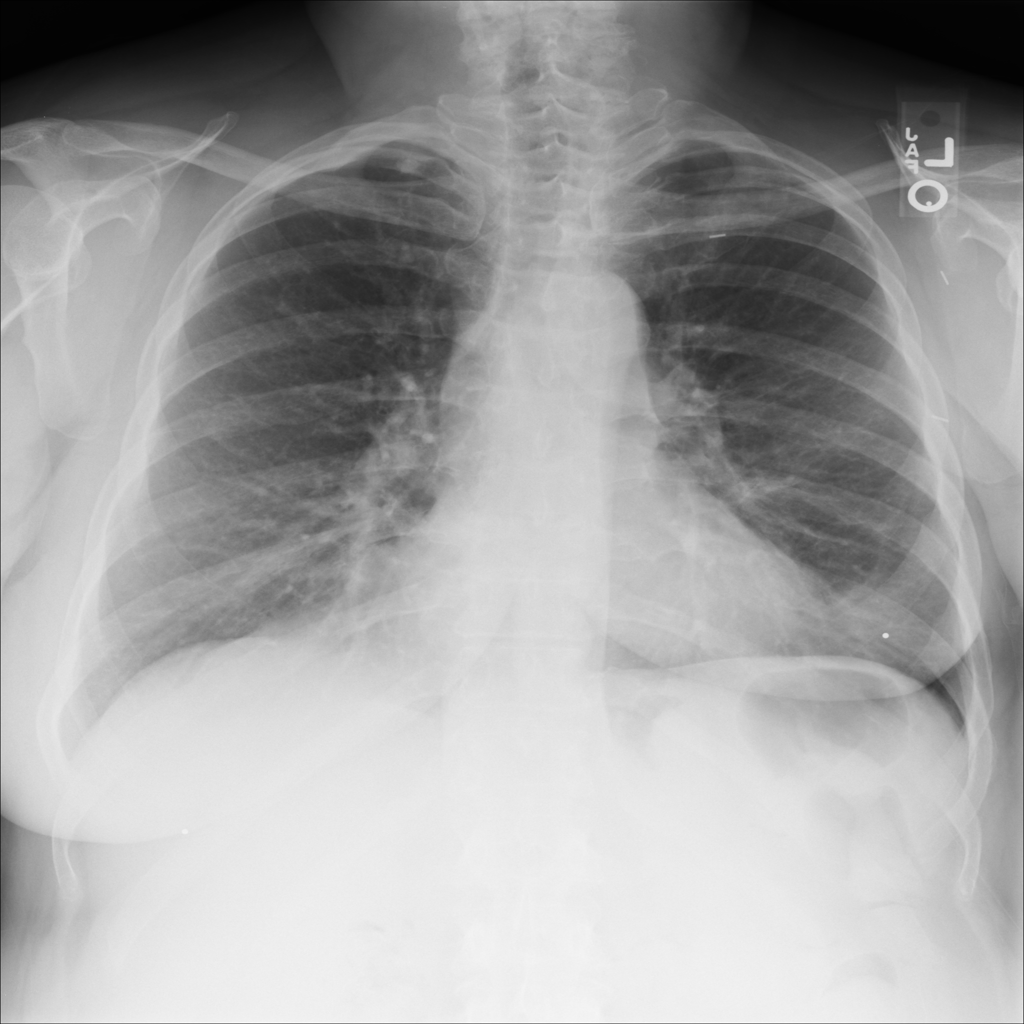

PAT-B708 · IMG-007Atelectasis

PAT-B708 · IMG-007

PA